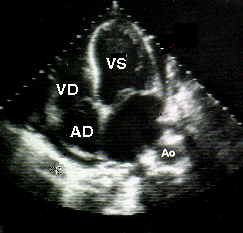

Ecocardiografice

clivare de spatiu pericardic sau spatiu transsonic (lichid) de diverse grosimi si localizari;

ingrosare de pericard cu eventuale depozite de fibrina (uneori libere in lichid).

Semne ecocardiografice:

lichid pericardic in cantitate mare (evidentiaza si dispunerea topografica a acestuia),

colaps AD, VD (protodiastolic) si AS,

EcoCG in tamponada cardiaca